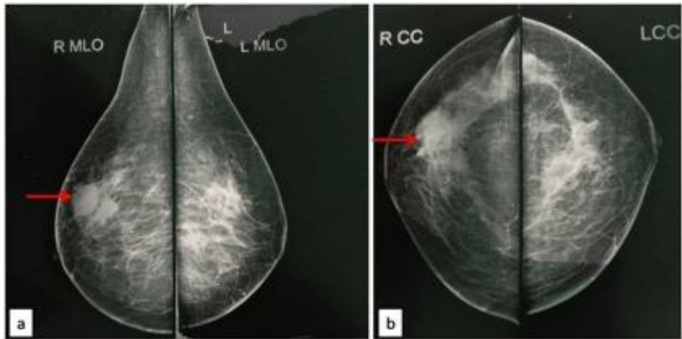

乳腺肿块常引发对恶性肿瘤的担忧,但某些罕见炎症性疾病可能表现出相似临床特征。嗜酸性乳腺炎作为良性炎症性疾病,在文献中仅少数病例记载,多与哮喘、Churg-Strauss综合征或高嗜酸细胞综合征相关,且通常伴有外周血嗜酸细胞增高。当患者同时出现周期性瘙痒性皮肤病变时,诊断更为复杂。本文报道的病例挑战了这一传统认知:患者乳腺肿块影像学呈现恶性特征(BIRADS 4级),但外周嗜酸细胞计数(AEC)仅72/μL,血清IgE水平正常(21 IU/ml),揭示了嗜酸性乳腺炎诊断的新维度。

该案例发表于《Surgical and Experimental Pathology》凸显其学术价值:影像学恶性特征(毛刺状边缘、囊实性结构)与良性本质的强烈对比,强调了组织病理学在乳腺疾病诊断中的不可替代性。未来需扩大样本量探索嗜酸性炎症的局部触发机制,为靶向治疗提供理论基础。